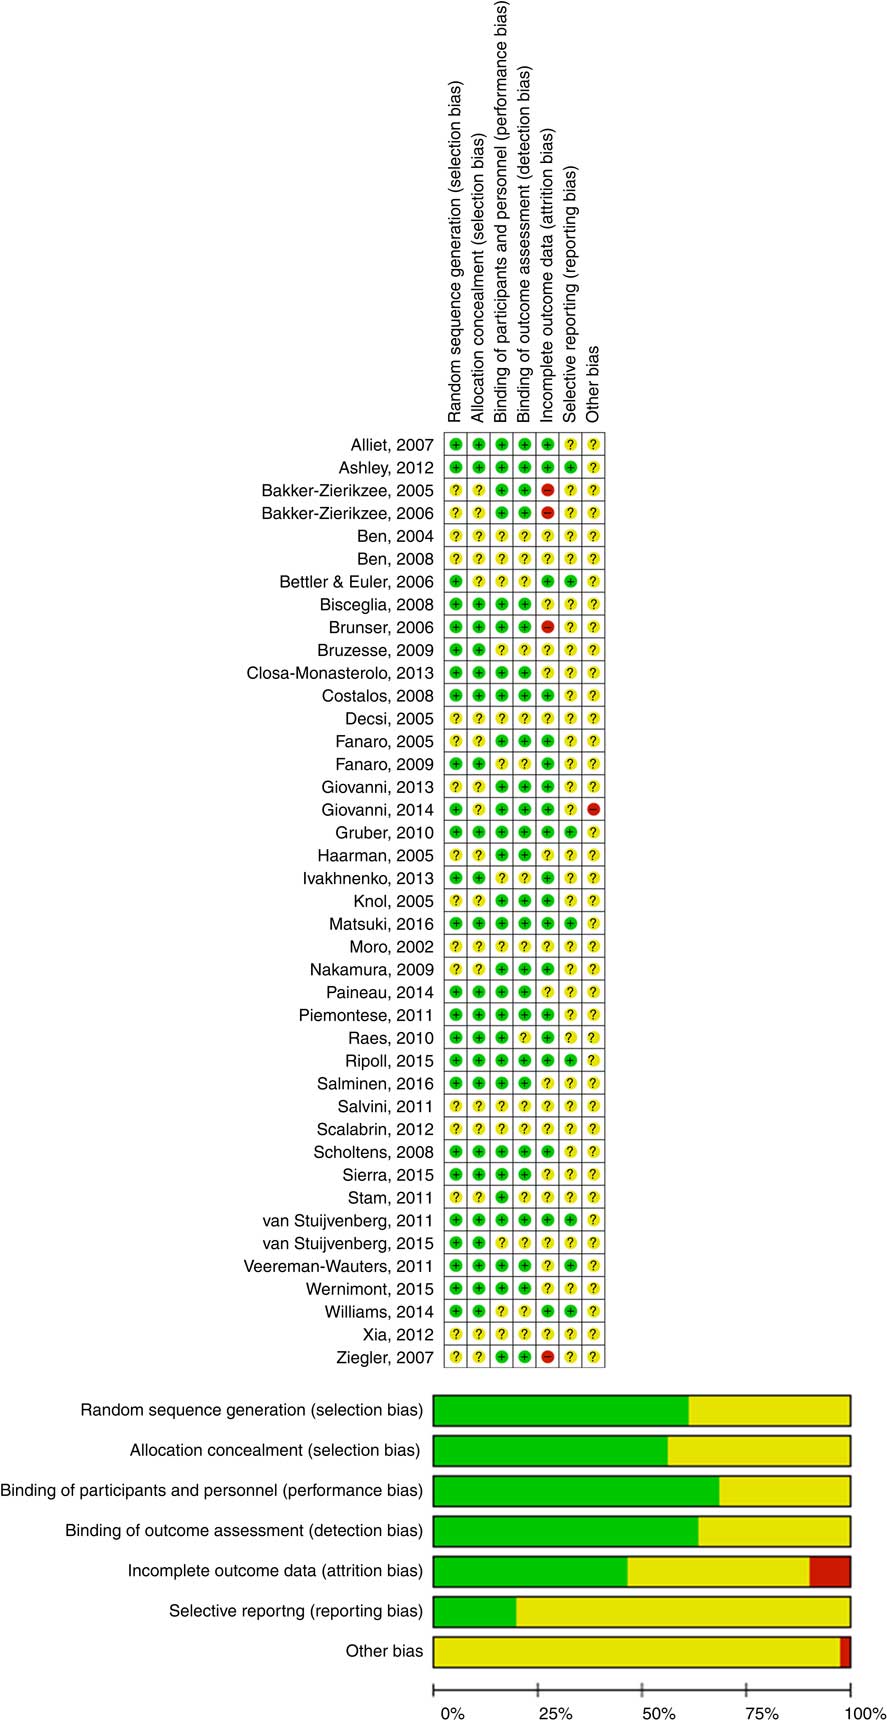

The Cochrane Collaboration’s tool for assessing risk of bias was used to establish the risk of bias. Type of randomisation method (selection bias), allocation concealment (selection bias), blinding of participants, personnel, intervention (performance bias), blinding of outcome assessment (detection bias), incomplete outcome data (attrition bias), selective reporting (reporting bias) and other forms of bias were considered( Reference Higgins and Green 3 ) (Fig. 1).

Fig. 1 Assessment of the risk of bias in included trials and the review authors’ judgements about each risk of bias item presented as percentages across all included studies. ![]() , Low risk of bias;

, Low risk of bias; ![]() , unclear risk of bias;

, unclear risk of bias; ![]() , high risk of bias. For a colour figure, see the online version of the paper.

, high risk of bias. For a colour figure, see the online version of the paper.

The quality of the included RCT varied (Fig. 1). Almost all of the included trials had a number of methodological limitations. The most common problems were a lack of description of randomisation procedures and/or allocation concealment and/or blinding.